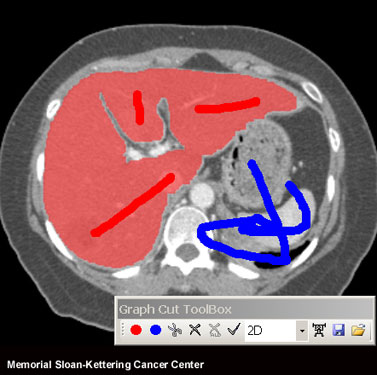

Example display of the software tool. The user trains the tool by

applying red and blue brush strokes to indicate liver and non-liver

regions. The tool calculates statistics from grey levels in the image to

identify the liver's outline (light red shaded area).

[Credit: Yu-Chi Hu /Memorial Sloan-Kettering Cancer Center]